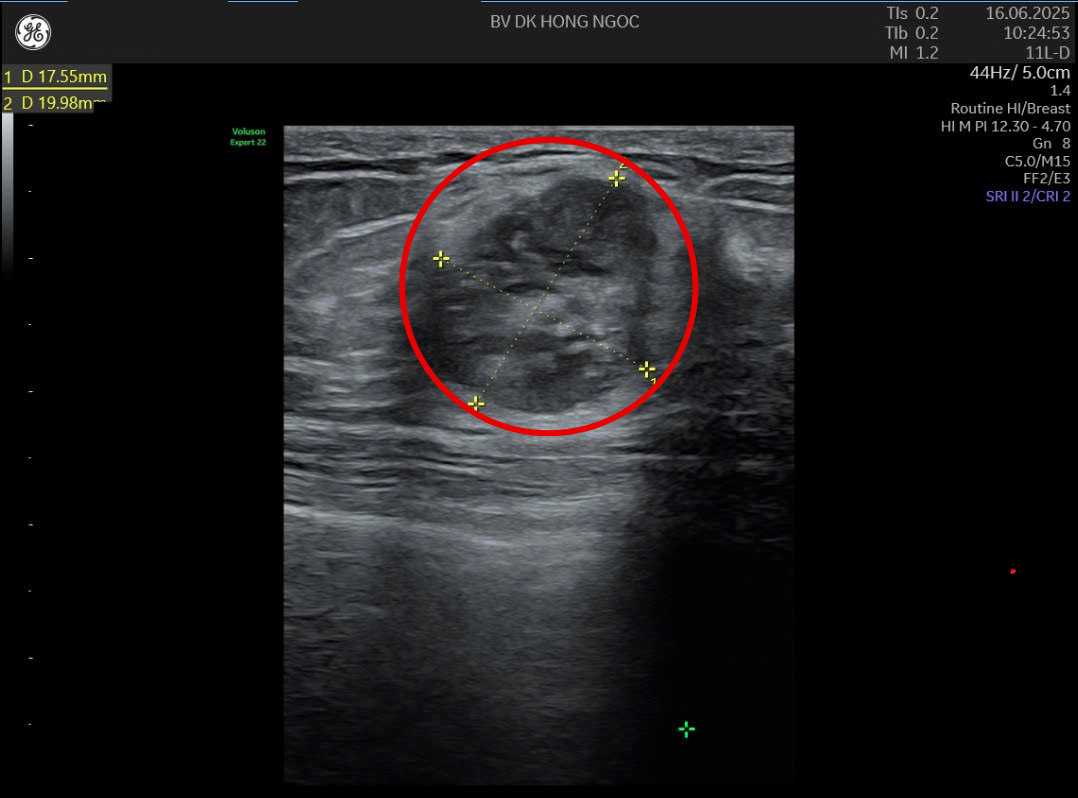

Hình ảnh khối u kích thước 1,7x1,9cm tại ngực trái của người bệnh

Kết quả siêu âm cho thấy phần ngực trái của chị Thơ có khối u kích thước 1,7x1,9cm, không di động, chẩn đoán ung thư vú giai đoạn II. "Cầm kết quả chẩn đoán mà tôi không thể bình tĩnh được, không thể tin là căn bệnh này lại rơi vào mình. Tôi vẫn tự hỏi: Tại sao không đau đớn gì mà lại là ung thư? - Chị Thơ trải lòng.